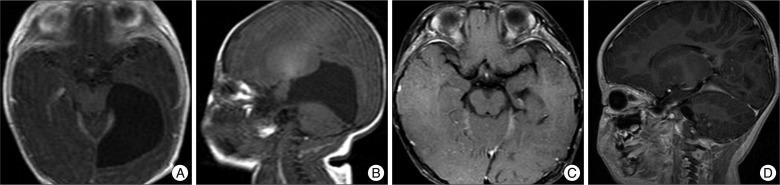

The indications and optimal surgical treatments for intracranial cysts are controversial. In the present study, we describe long-term clinical and neuroimaging results of surgically treated intracranial cysts in children. The goal of this study is to contribute to the discussion of the debate.

This study included 110 pediatric patients that underwent surgeries to treat intracranial cysts. Endoscopic cyst fenestrations were performed in 71 cases, while craniotomies and cyst excisions (with or without fenestrations) were performed in 30 patients. Cystoperitoneal shunts were necessary for nine patients. Long-term results were retrospectively assessed with medical and neuroimaging records.

Clinical and radiological improvement was reported in 87.3% and 92.8% of cases, respectively, after endoscopic neurosurgery, and in 93.3% and 100% using open microsurgery whereas 88.9% and 85.7% after shunt operation. There were no statistical differences in clinical outcomes (p=0.710) or volume reductions (p=0.177) among the different surgeries. There were no mortalities or permanent morbidities, but complications such as shunt malfunctions, infections, and subdural hematomas were observed in 56% of the patients that had shunt operations. A total of 13 patients (11.8%) underwent additional surgeries due to recurrences or treatment failures. The type of surgery performed did not influence the recurrence rate (p=0.662) or the failure rate (p=0.247).

Endoscopic neurosurgeries are less invasive than microsurgeries and are at least as effective as open surgeries. Thus, given the advantages and complications of these surgical techniques, we suggest that endoscopic fenestration should be the first treatment attempted in children with intracranial cysts.